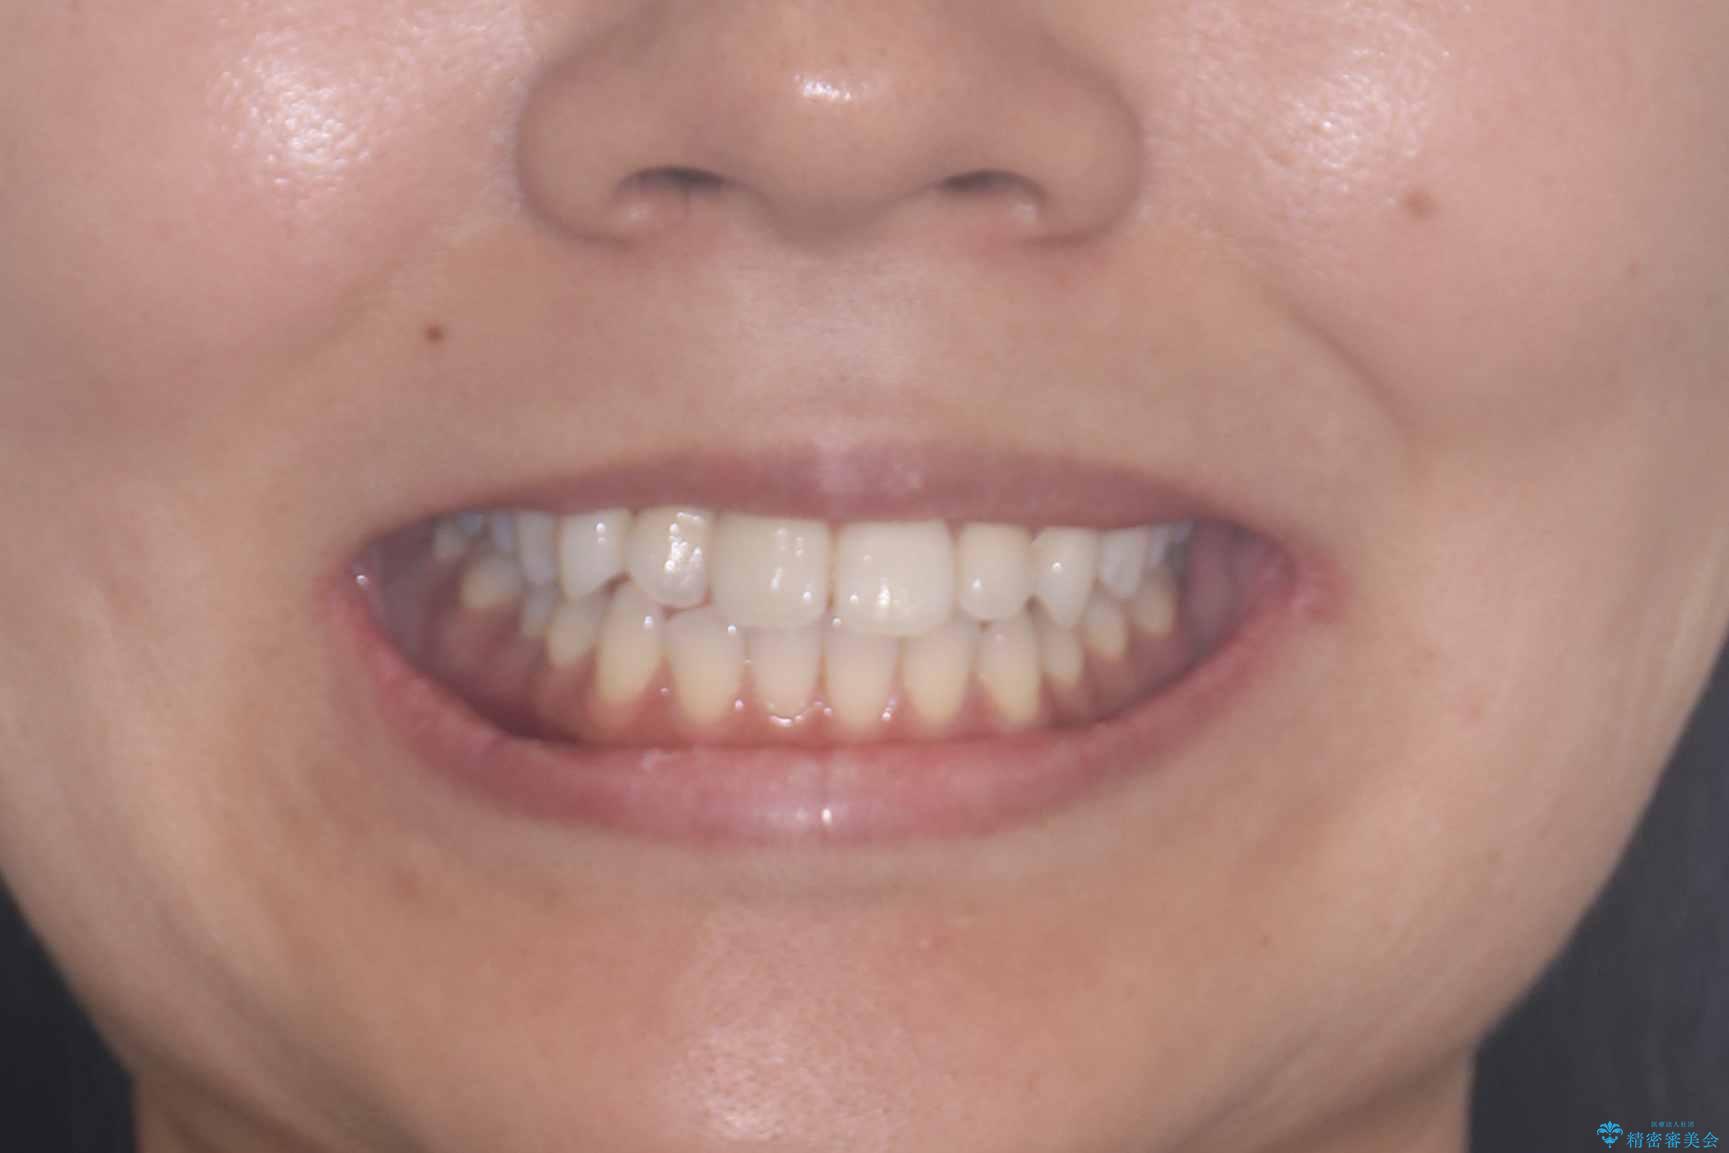

- 歯の捻じれやデコボコを主訴にご来院された患者様です。

治療は、白いコーティングが施されたワイヤーを使用した審美性の高い装置にて行っています。

装置には、ワイヤーに白いコーティングが施された審美性の高いワイヤー矯正装置を使用し、

治療中も目立ちにくい配慮を行いました。

その結果、約10ヵ月という比較的短期間で歯列と咬み合わせが整い、機能面・審美面ともに良好な結果を得ることができました。